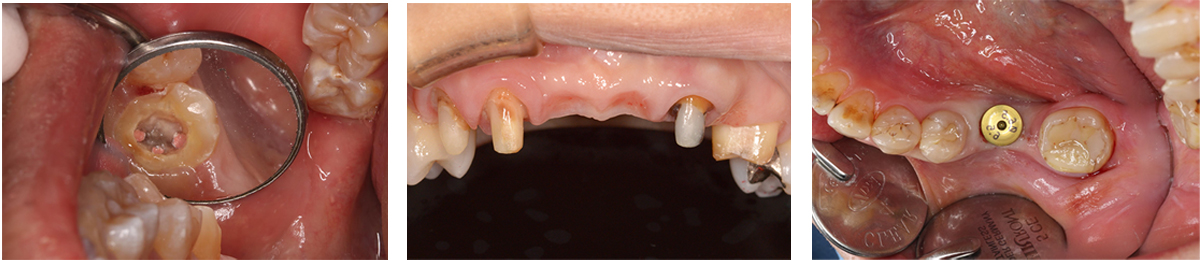

咬合再構成も含めた審美的な補綴治療を学べます。

インプラント治療

最近はインプラントや矯正、高度先進医療に注目が行きがちですが、それらの治療は齲蝕や歯周病のリスクコントロールが無い口腔内に行ったのでは永続性が高い治療とは言えません。

当院では口腔内で最もありふれた病気であり、且つ歯を喪失するほとんどの原因である齲蝕、歯周病のリスクコントロールを患者さんと二人三脚で行っていくことを診療のベースとしています。